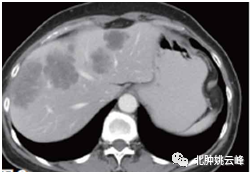

结直肠癌患者超过50%会发生肝转移:《中国结直肠癌肝转移诊断和综...

结直肠癌发生肝转移,不要轻易放弃治疗,五年生存率可以达到近50%...

肝转移?腹膜转移?晚期大肠癌(结直肠癌)就“无可救药” 了吗?...

结直肠癌肝转移能否手术治疗?

当肠癌发生转移,临床仍有手术机会